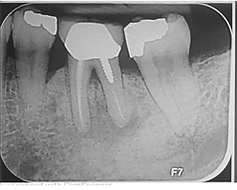

针对较小的口腔骨缺损,牙槽和种植体周围骨保留(即刻种植)

针对中度口腔骨缺损的牙槽骨保留